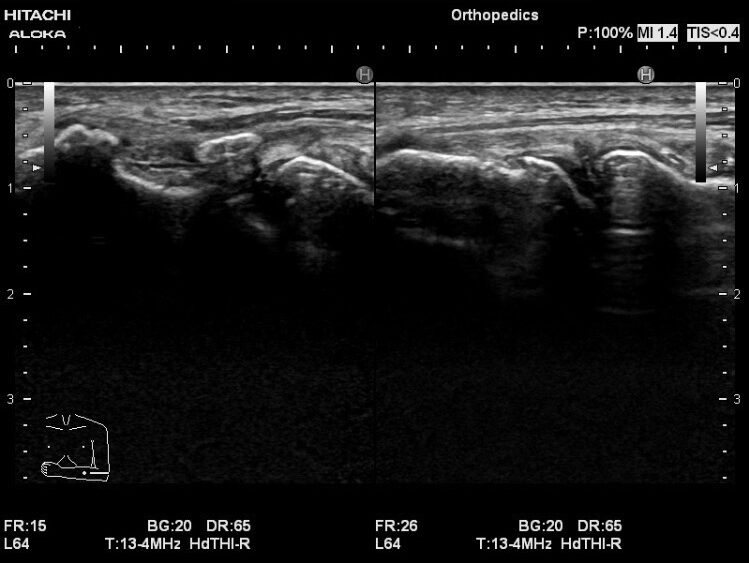

このエコー画像では、短橈側手根伸筋の腫脹と、長年テニスをプレーし続けた事で発生した外側上顆の変形が確認できます。